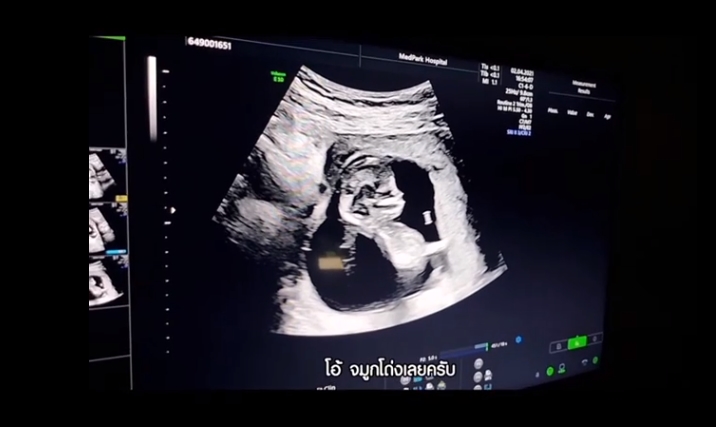

ตูน บอดี้สแลม ก้อย รัชวิน เฉลยเพศลูกคนแรกแล้ว จะเป็นผู้ชายหรือผู้หญิงกันน้า งานนี้ได้รู้แล้วว่าจะเป็นพ่อหรือแม่ที่ต้องเสียเงิน 1 ล้านบาท บอกเลยเตรียมชุดให้ตั้งแต่ในท้อง ในที่สุด (30 พฤษภาคม 2564) ก็มาถึงช่วงเวลาที่แฟน ๆ รอคอย เมื่อว่าที่คุณพ่อ ตูน บอดี้สแลม และคุณแม่ ก้อย รัชวิน ได้มาเฉลยเพศของลูกคนแรกให้ได้รู้กันแล้ว ซึ่งคุณพ่อตูน เผยว่า ตัวเองรู้ผลเพศลูกก่อน แต่อุบเงียบไว้ เพราะตอนที่ไปอัลตราซาวด์รอบแรกคุณหมอคาดว่าเป็นผู้หญิง และทางก้อยเองก็อยากได้ลูกสาว ส่วนพี่ตูนอยากได้ลูกชาย จนมีการพนันกันเป็นเงิน 1 ล้านบาท ต่อมาทางคุณหมอได้ส่งเพศของลูกมาให้ทางคุณพ่อ และเมื่อถึงเวลาเฉลยนั้น ก็พบว่า เบบี๋น้อยคนแรกคือลูกชายนั่นเอง งานนี้พี่ตูนซึ่งชื่นชอบฟุตบอลทีมสเปร์สก็บอกว่า วันแรกที่ลูกเกิดพี่ตูนจะให้ใส่ชุดฟุตบอลทีมสเปอร์สเลยทีเดียว ซื้อมาทุกช่วงอายุเตรียมไว้เรียบร้อย พอก้อยรู้ปุ๊บว่าได้ลูกชาย ก็ดีใจไม่แพ้พี่ตูน เพราะรู้ว่าพี่ตูนอยากได้ลูกชายนั่นเอง เรื่องชื่อลูกนั้น ตอนนี้ก็มีชื่อที่เรียกกันอยู่แล้ว เป็นได้ทั้งชื่อเล่นและชื่อจริงก็ได้ ใบ้ว่าเป็นชื่อเกี่ยวกับสถานที่ที่เรามีความสุข แต่ต้องดูก่อนว่าจะใช้ชื่อนี้เป็นชื่อจริงหรือเปล่า แต่ชื่อเล่นใช้ชื่อนี้แน่ ๆ ใบ้ว่า 2 พยางค์ ในส่วนของการอัลตราซาวด์นั้น ก็รู้เลยว่าเบบี๋น้อยแข็งแรงสุด ๆ เพราะมีการเล่นขี่ม้ามาตั้งแต่ในท้องคุณแม่เลย บ่งบอกถึงความเป็นลูกชาย แถมยังจมูกโด่งหล่อเหลามาแต่ไกลเลยทีเดียว ซึ่งสรุปแล้วนั้น แม่ก้อยต้องเป็นคนจ่าย 1 ล้านบาท เพราะทายเพศลูกผิดนั่นเอง โดยจะเก็บเป็นเงินเข้าบัญชีให้ลูกไว้ กระปุกดอทคอม ขอแสดงความยินดีกับแม่ก้อย และพ่อตูน ด้วยนะคะ ดูท่าแล้วลูกชายคนนี้จะไม่ธรรมดา เพราะเบบี๋น้อยเล่นซนมาตั้งแต่ในท้องคุณแม่ น่าจะสนุกแน่ ๆ เลยค่า